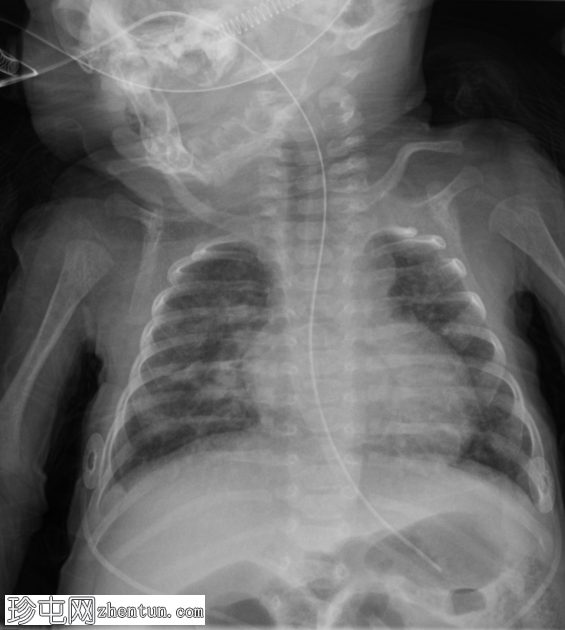

支气管肺发育不良

就诊

疑似支气管

肺

发育不良 (BPD)。

呼吸

窘迫综合征 (RDS) 病史。表现为发育迟缓。孕29周出生。

患者资料

年龄:8周

性别:女

X光片

双侧肺实质影粗糙,以中央/肺门周围为主。肺容积在正常范围内。

经食管导管终止于胃部。无胸腔积液或气胸。

心脏

大小和形态正常。无急性骨异常。

病例讨论

本例为支气管肺发育不良 (BPD) 病例。

该婴儿早产(孕29周)。出生时,她出现了呼吸窘迫综合征的体征,需要插管,这使她患BPD的风险更高。